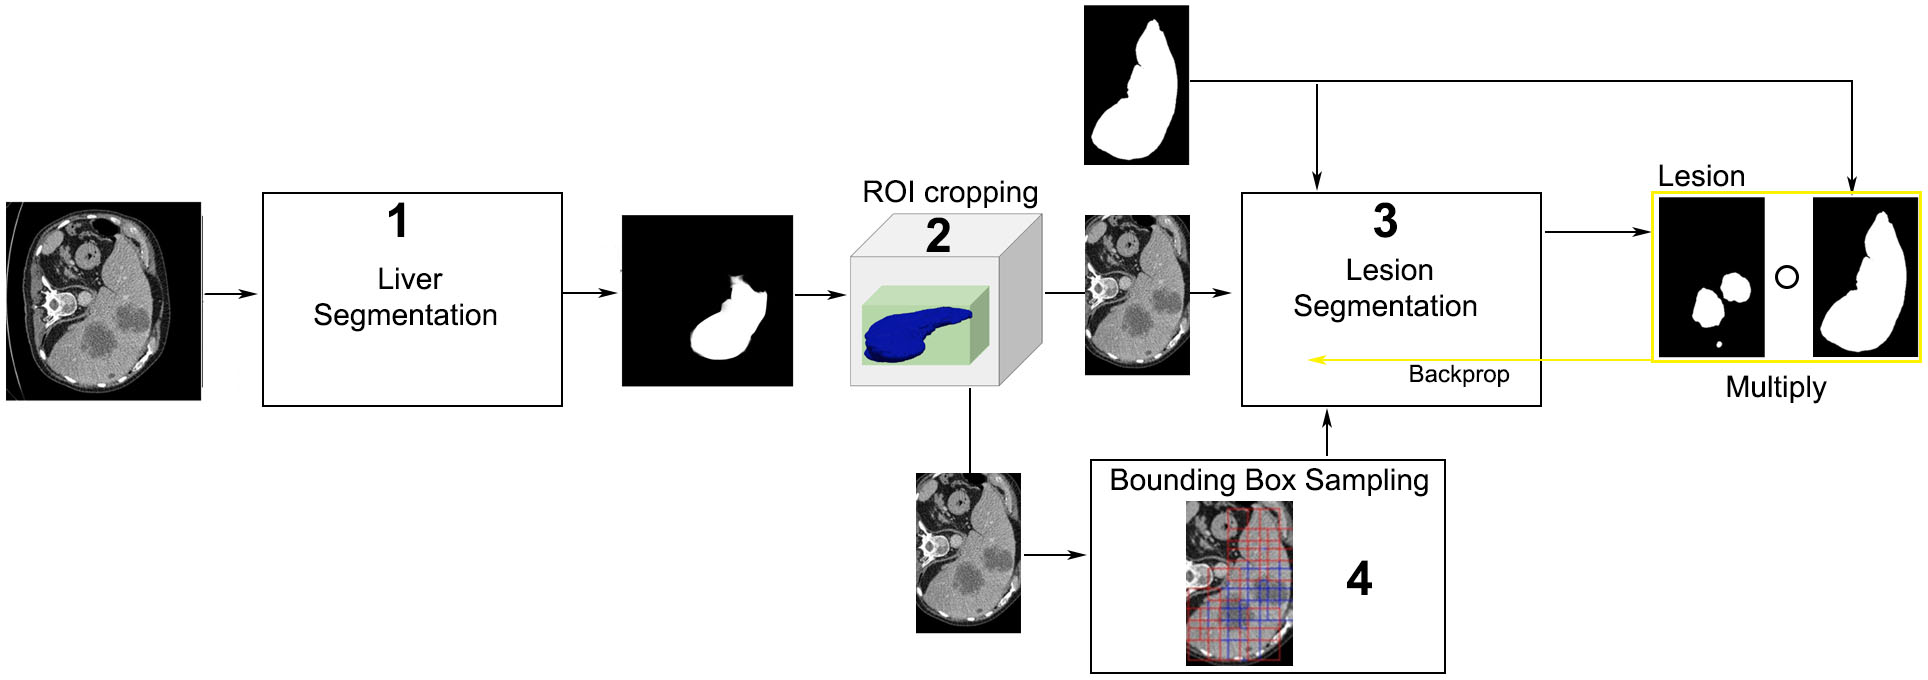

Being inspired from DRIU, the algorithm presented uses side outputs after each convolutional stage, all contributing to the final output. As the algorithm performs also lesion segmentation, the general architecture comprises multiple modules: liver segmentation, ROI cropping, lesion detector, lesion segmentation. An overview of the general architecture is presented in Figure 3.4, and a detail of the liver segmentation architecture is presented in Figure 3.5. The lesion segmentation architecture starts from the same architecture used for liver segmentation, with different added enhancements.

3.2.5 ROI cropping

After the liver segmentation, the outputted volume is fed to the ROI cropping, where the liver segmentation volume is cropped slice by slice around the liver ROI, as shown in Figure 3.4, module 2. The resulting smaller volume is afterwards used as input for the lesion detector and the lesion segmentation modules. The number of positive pixels in each slice of the predicted liver masks resembles a Gaussian, so after a fitting of a Gaussian, a mean and variance are computed. The fitting is used to remove false positives, as all images outside a certain threshold are not likely to contain any lesion. As such, a significant number of false positives is removed, at the expense of a few false negatives.

3.2.6 Using the liver segmentation for the lesion segmentation

The liver segmentation is used in the process of lesion segmentation as a mask which limits back-propagation only to those pixels which belong to the liver segmented ROI. This way, only those pixels which can belong to the liver are used for the lesion segmentation learning process, and also, the process is more balanced as there are less negative pixels in the image. For this stage, the balancing term includes just the pixels contained inside the liver. This process is illustrated in Figure 3.4 (module 3 - right).

Masking

As depicted in Figure 3.4, to perform the lesion segmentation, only those pixels predicted as belonging to the liver are considered. This improves the detection accuracy at the expense that if there is a mistake in the liver segmentation , this will propagate.